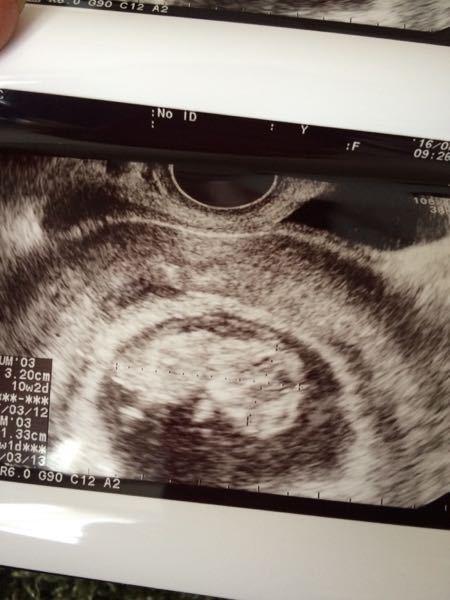

エコー写真出ます 妊娠10週です 頭のところが二箇所黒い丸になってるの 妊娠 教えて Goo

胎児の大きさの平均は2~3センチ程度、胎のう5~6センチ程度、体重は3~12グラム程度, Facebook で共有するにはクリックしてください ( 妊娠10週目(10w0d~6d)のエコー写真とエピソード|妊娠3ヶ月 妊娠10週目の時期は大体1週間~2週間おきに病院へ妊婦健診に行くことが多いため、エコー写真を撮るのも2回目、3回目になる方もいるでしょう。 子宮の大きさは握りこぶしほどになり、ママのお腹もすこしぽっこりしてきます。 この頃の赤ちゃんはだいぶ人間らしい形になり、エコー写真を撮る際に足を このようにダウン症児の検査方法には色々なものがあるため、それぞれの特徴を理解しましょう。 →妊娠10週目でダウン症はエコーでわかるのか? 妊娠中に少しでも心配を少なくするには? 葉酸はサプリから摂るのがいいのはどうして? ダウン症エコー検査は、ママにとって、不安なものです。 何か、自分に出来る事はないかと、どのママも、ダウン症エコー

妊娠10週目 10w0d 6d のエコー写真とエピソード 妊娠3ヶ月 Cozre コズレ 子育てマガジン

妊娠10週 つわりのピーク 妊婦の症状や赤ちゃんの大きさ エコー写真付き ままのて